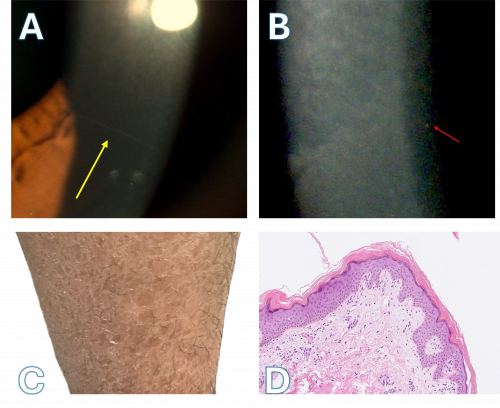

Cornea farinata is a relatively common, asymptomatic corneal degenerative disease characterized by numerous small, fine, dust-like opacities in the pre-Descemet's membrane often bilaterally. The etiology, risk factors, and pathophysiology have been revealed to an extent but more research is needed to completely understand these aspects of this condition. Though mainly diagnosed via slit-lamp examination, confocal microscopy is very helpful in differentiating cornea farinata from similar diseases.

Cornea Farinata, also known as “floury cornea”[2] [3], is a relatively common asymptomatic, degenerative, and age-related corneal disease characterized by numerous small, fine, and often bilateral dust-like opacities which resemble wheat flour. These opacities in the deep central corneal stroma have a gray-white or tan-brown color.[2] [3][4] [5] [6] [7] [8] It was first described by Alfred Vogt in 1923.[2] [3] [5] [9]

This entity presents with numerous fine, dust-like, cytoplasmic, hyper-reflective, gray-white and tan-brown opacities which are distributed diffusely and evenly in the posterior central corneal stroma, the area also referred to as the pre-Descemet’s membrane.[5] [6] [7] [13] [14] [15] [16] [17] There are usually no accompanying abnormalities or opacities in Descemet’s membrane, anterior-to-mid-stromal layers, or corneal epithelial or endothelial cell layers.[6] [7] The opacities present on slit-lamp microscopy and confocal microscopy are composed of intracytoplasmic vacuoles containing lipofuscin-like inclusions histopathologically and can cause abnormally large stromal keratocytes.[3] [4] [5]

Cornea farinata is diagnosed clinically via visual examination using slit-lamp microscopy or confocal microscopy. Confocal microscopy provides enhanced detail of the opacities present in this condition.[2] [3] [4] [6] [7]

The fine, dust-like opacities present are best visualized on slit-lamp examination with retro-illumination of the iris.[3] [4] [6][18] Specific differentiating features of this condition are that no opacities will be observed in the anterior or mid-stroma of the cornea and abnormalities of Descemet’s membrane and corneal epithelial or endothelial cell layers will not be seen .[6] [7]

Although biomicroscopy is a useful tool for detecting stromal opacities, confocal microscopy is an important diagnostic procedure in differentiating corneal farinata from other similar corneal dystrophies and degenerations.[6] [7]